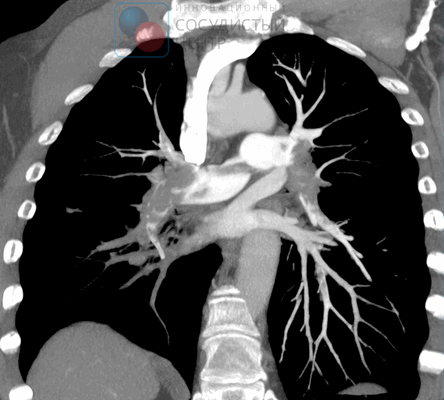

Компьютерная томография и КТ-ангиопульмонография

Основными задачами ангиографической диагностики являются определение степени тяжести легочной гипертензии, уточнение характера поражения легочного русла посредством ангиопульмонографии, выявление/исключение коронарной болезни. Проведение катетеризации в изолированном виде без качественной ангиопульмонографии у больного с четкими признаками ХТЭЛГ нецелесообразно. Это исследование должно дать четкую информацию врачам для решения вопроса об операбельности больного и тяжести его состояния. Гемодинамическими критериями постэмболической легочной гипертензии, выявляемыми при катетеризации правых отделов сердца, являются: среднее давление в легочной артерии (ДЛА) выше 25 мм рт. ст., давление заклинивания легочной артерии (ДЗЛА) ≤ 15 мм рт. ст., ЛСС > 2 ЕД. по Вуду (160 дин. сек см- 5 ) при наличии множественных стенозирующих и/или окклюзирующих поражений ветвей легочной артерии различного калибра.